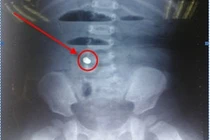

Cứu sống bệnh nhi bị tắc ruột do nuốt phải dị vật

(Kiến Thức) - Mới đây, Khoa ngoại, Bệnh viện Nhi trung ương đã tiếp nhận và mổ cấp cứu một trường hợp tắc ruột do nuốt phải dị vật.

Đó là trường hợp bệnh nhi P.D.K trú tại Cổ Nhuế, Từ Liêm, Hà Nội, 14 tháng tuổi vô tình nuốt phải các hạt nhỏ đính trên mũ vương miện đồ chơi. Theo các bác sĩ, bệnh nhi nhập viện trong tình trạng mệt mỏi, nôn dịch vàng, bụng mềm, chướng nhẹ, ấn đau trên rốn.

Thông tin từ người nhà bệnh nhân cho biết, khoảng 3 ngày trước khi nhập viện, cháu K. quấy khóc, ăn uống kém hơn những ngày trước đó. Ngày 10/2, trẻ có quấy khóc tăng lên, kèm theo nôn dịch màu xanh sau ăn uống, trẻ không đi ngoài được trong 3 ngày trước khi vào viện. Bố mẹ cháu K. cho biết, trước đó cháu có chơi chiếc mũ vương miện (không rõ xuất xứ), có khả năng trẻ vô tình nuốt phải các hạt nhỏ đính trên mũ mà gia đình không biết.